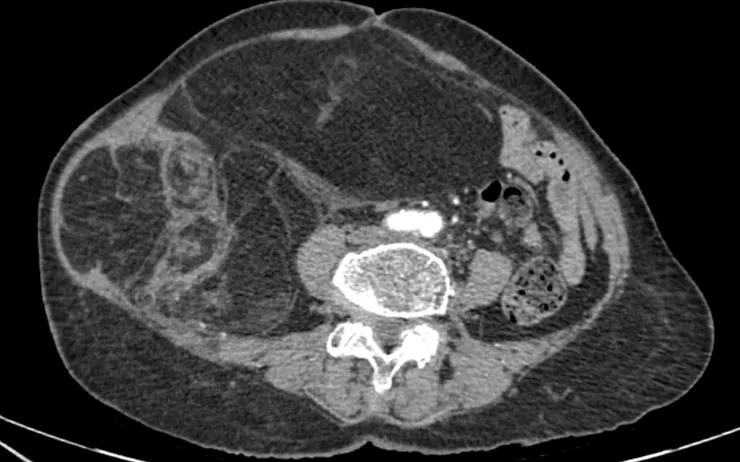

Phim chụp CT ổ bụng

Chẩn đoán hình ảnh (CT ổ bụng có thuốc cản quang) cho thấy khối choán chỗ sau phúc mạc, kích thước 28 × 15 cm, cấu trúc hỗn hợp tổ chức mỡ – đặc , đè đẩy tạng trong ổ bụng nhưng không có dấu hiệu xâm lấn các tạng lân cận. Kết hợp lâm sàng và hình ảnh học, bệnh nhân được chẩn đoán sarcoma mỡ sau phúc mạc.